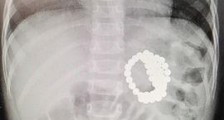

- “熊孩子”误吞21颗磁珠 专家提醒幼儿远离此类玩具

- 近日,刚满2周岁的小坤(化名),误吞巴克球磁珠2天仍未排出,心急火燎的家人带小坤前往安徽省儿童医院普外二病区求助。接诊专家问诊、触诊后,X线检查结果显示:小坤肠道内部的磁珠...

- 将磁力珠当成糖果 重庆2岁小女孩吞下了51颗

- FPA豪仕阅读网 小女孩的平片影像。FPA豪仕阅读网FPA豪仕阅读网 手术取出的磁力珠。FPA豪仕阅读网 磁力珠被作为减压益智的玩具,可以随意凹造型,深受家长和小朋友们喜...